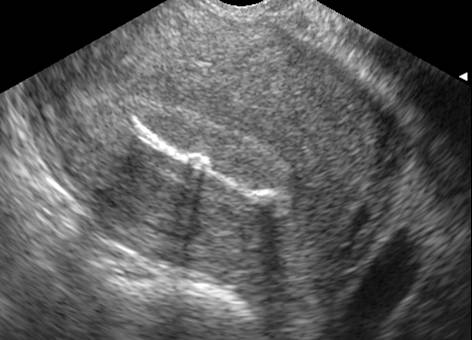

DIU en place, coupe transversale